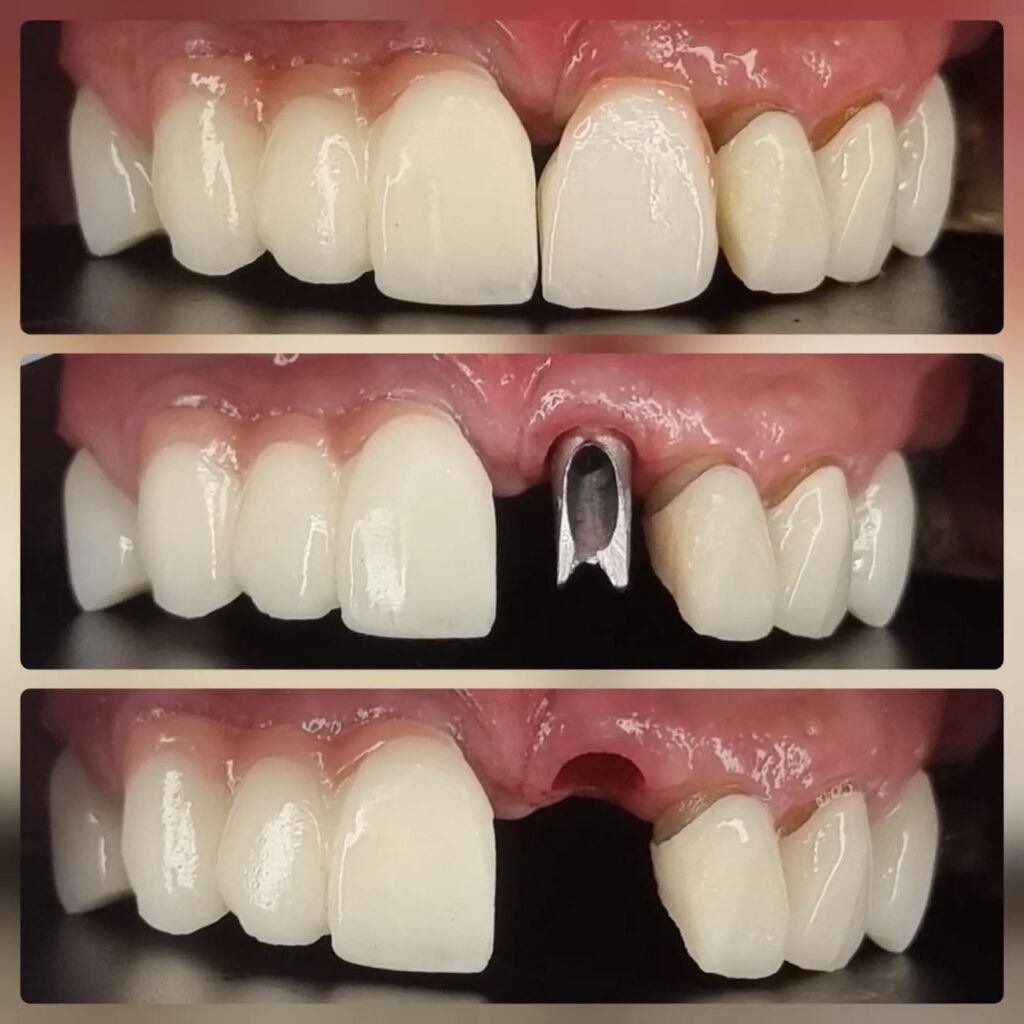

کاشت ایمپلنت دندان

اطمینان حاصل کردن از اینکه دندانهایتان به نحوی زیبا و طبیعی جایگزین شدهاند، از اهمیت بسیاری برخوردار است. ایمپلنت دندان به عنوان یک روش درمانی دائمی در دندانپزشکی شناخته میشود که حاصل آن، یک دندان زیبا و طبیعی در دهان شما خواهد بود.

هرچند که این روش درمانی هزینهی بیشتری نسبت به روشهای دیگر دارد، اما ارزش زیبایی که ایجاد میکند، قابل انکار نیست. ایمپلنتها به قدری شبیه به دندانهای طبیعی هستند که به سختی میتوان آنها را از دیگر دندانها تشخیص داد.